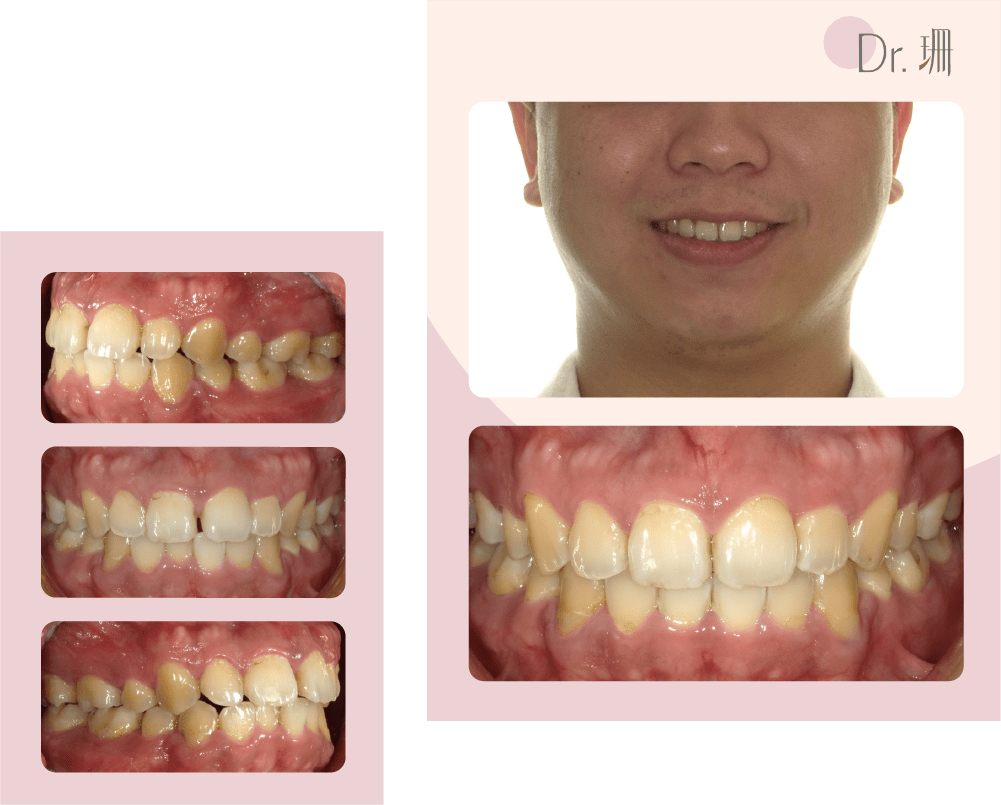

/ 主訴

牙齒擁擠、深咬、上下門牙水平距離大

/治療方式

利用上排智齒的空間 搭配 TAD 錨定裝置及橡皮筋將上排牙齒往後退

隱適美矯正牙齒過程

牙齒矯正前後外觀及牙齒變化